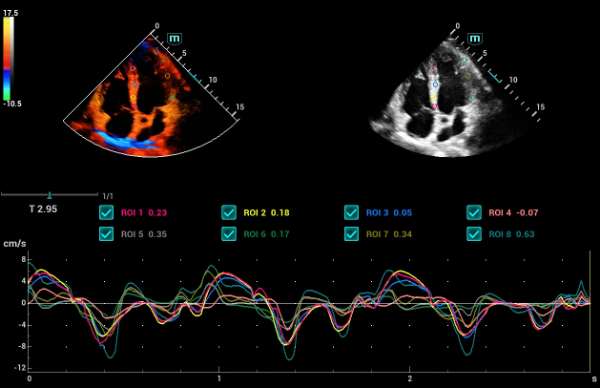

- TDI – Tissue Doppler Imaging

- TDI Quantification Analysis Software

- Tissue Tracking with Quantitative Analysis